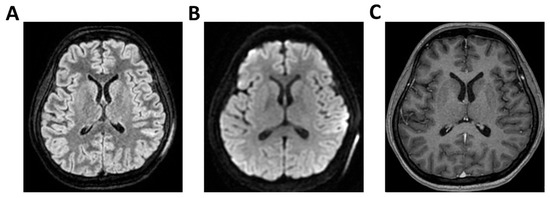

Background: Meningoencephalitis is a complex inflammatory condition of the CNS that can result in significant morbidity and mortality in critically ill adults. Accurate and timely neuromonitoring is essential for guiding management and improving outcomes. This study aimed to descriptively evaluate the prognostic value of early TCCD monitoring, particularly the pulsatility index, and its integration with conventional and perfusion MRI in patients with meningoencephalitis. Methods: We present an observational, retrospective, cohort study involving ten adult patients (median age 56 years, IQR 45.5–68.5; mean 55.9, range 35–76) with neurological syndromes caused by suspected or confirmed infectious meningoencephalitis. Etiologies included bacterial meningitis/meningoencephalitis (50%), viral meningoencephalitis (10%), neurotoxoplasmosis (10%), progressive multifocal leukoencephalopathy (10%), and undetermined origin (20%). Patients underwent TCCD and MRI within 24 h. In five cases, standard MRI sequences were acquired, while in the remaining five, perfusion imaging was performed using Arterial Spin Labelling (ASL). A favorable outcome was defined as survival with neurological recovery (Glasgow Outcome Scale > 5) at ICU discharge. Results: TCCD-derived PI provided valuable information on cerebral hemodynamics. PI values ≤ 1.25 were associated with favorable clinical outcomes and symmetrical MRI findings. Conversely, PI > 1.25 correlated with poor prognosis and often preceded MRI-detectable structural damage. When combined with ASL, PI mirrored the detected perfusion asymmetries and was associated with poor prognosis in fatal cases. Conclusions: Bedside TCCD can offer real-time assessment of cerebrovascular dynamics and, when integrated with conventional and ASL MRI, could enhance the understanding of pathophysiological processes in meningoencephalitis, supporting timely and informed decisions in neurocritical care.